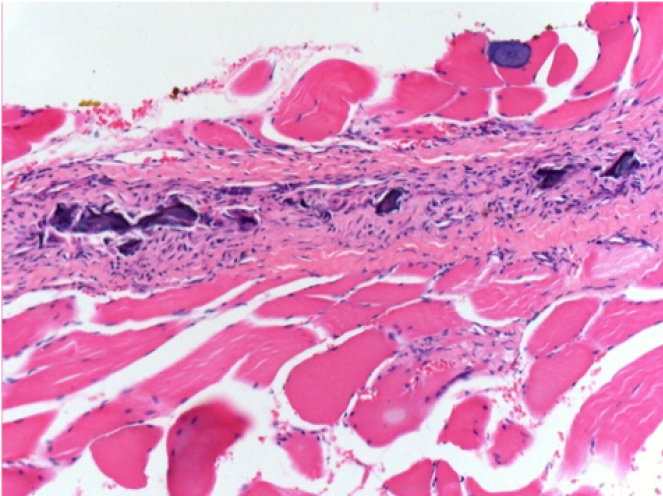

1 month after Endopeel Injection

1 month after Endopeel Injection 0.1ml in the right pretibial muscle.

What is seen in black on the pictures is not a necrosis like could imagine some scientifics !

In fact, 4 conclusions have to be taken in consideration

- an artefact of coloration

- an absence of necrosis

- an apoptosis

- a bioregenerative process

L : Control-100xD30

R:100xD30

R :400xD30